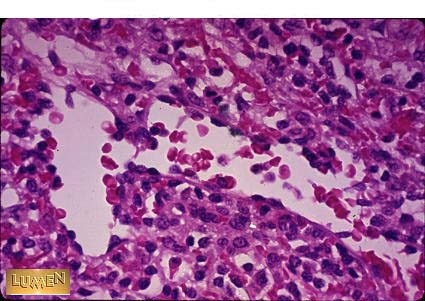

This is the spleen, is this red pulp or white pulp?

Answer

Red Pulp, note sinusoids